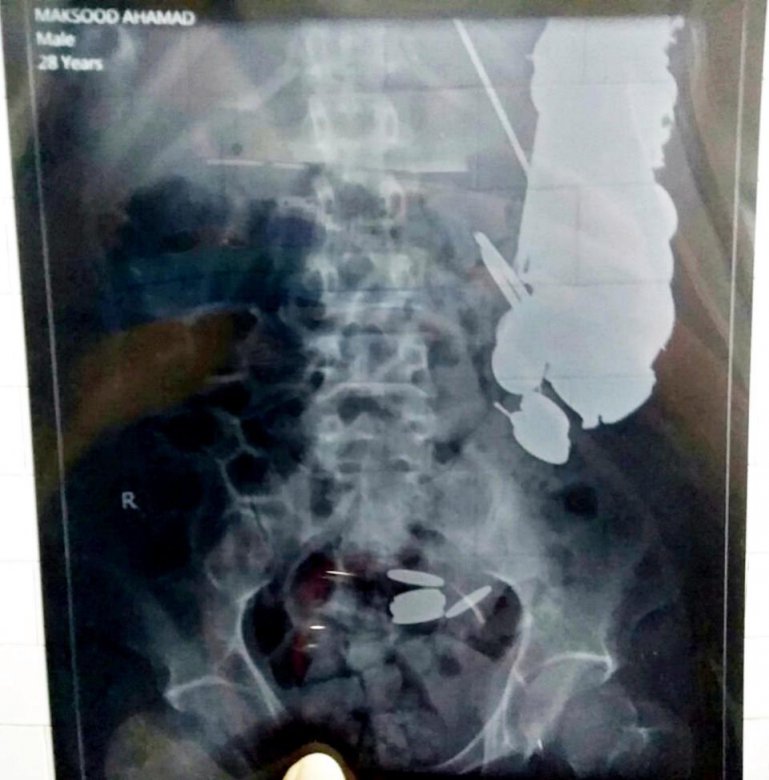

35-летний Максуд Кхан (Maksud Khan) из Индии поступил в больницу с болями в животе и врачи провели эндоскопию, чтобы выяснить причину. Они были поражены, когда обнаружили в желудке сотни монет, 1,5 кг гвоздей, десятки бритвенных лезвий, осколки стекла, камни, и шестидюймовый кусок ржавого железа. Хирурги в больнице Санджай Ганди в Сатна, Мадхья-Прадеш, Индия, сразу прооперировали мужчину и удалили 7 кг посторонних предметов.

Максуд работал в качестве водителя тук-тука и часто проглатывают монеты, переданные ему клиентами. Родственники утверждают, что он впал в депрессию и стал глотать металлические предметы, запивая водой. Он жаловался на боли в желудке в течение трех месяцев, пока не обратились в больницу. Операцию сделали в последний момент, индиец мог умереть в ближайшее время. Теперь мужчина в безопасности и поклялся больше подобного не делать.